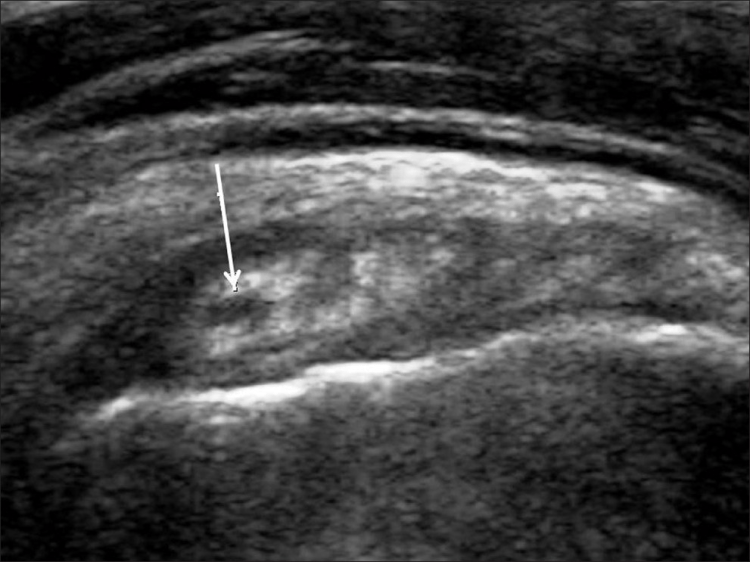

Los desgarros del manguito de los rotadores son la patología más común que se encuentra en los exámenes de ultrasonido del hombro.[7] La incidencia de lágrimas aumenta con la edad. Los desgarros de tendones se pueden clasificar de acuerdo con el grado de falla de la fibra, que van desde desgarros completos [Figura 7], desgarros de espesor total [Figuras 8, 9], desgarros de espesor parcial [Figuras 10-12] y desgarros intrasustancia [Figura 13 ]. Un desgarro agudo suele ir acompañado de derrame articular o bursal [Figura 12]. [7-9] La ausencia de derrame generalmente se relaciona con desgarros crónicos.[9] En un metanálisis sobre la precisión de la resonancia magnética, la artrografía por resonancia magnética y la ecografía en el diagnóstico de desgarros del manguito de los rotadores, la ecografía ofreció una alta sensibilidad y especificidad para la evaluación de los desgarros del manguito de los rotadores de espesor total (92,3 y 94,4 %, respectivamente) con 85,1 % y 92 %, respectivamente para todas las lágrimas.[7] El desgarro de espesor parcial aparece como un defecto o hendidura hipoecogénica en el tendón, afectando solo una parte de su espesor, mientras que un desgarro de espesor total se extiende desde la bolsa hasta la superficie articular del tendón. Un desgarro completo es un desgarro de espesor completo que afecta todo el ancho del tendón. El tendón se retrae medialmente, y la cantidad de retracción depende de la edad del desgarro. En las roturas crónicas, el tendón desaparece por debajo del arco coracoacromial, dejando la cabeza humeral descubierta por el supraespinoso, el denominado signo de la "cabeza desnuda". Los hallazgos de la ecografía incluyen la falta de visualización del tendón y la hernia del músculo deltoides. Los desgarros intrasustancia permanecen localizados en el tendón sin afectar sus márgenes. Los desgarros intrasustancia y de espesor parcial pueden ser difíciles de diferenciar de la tendinopatía focal.

Las patologías no relacionadas con desgarros del manguito rotador que se encuentran con más frecuencia son la tendinosis del manguito rotador [Figura 14], la tendinitis calcificante del manguito rotador [Figura 15] y el pinzamiento del tendón subacromial [Figura 16]. Vale la pena señalar que, en tales casos, se pueden desarrollar desgarros debido a la debilidad del tendón [Tabla 2].[79] La tendinosis o tendinopatía del manguito de los rotadores se presenta como inflamación del tendón con una ecotextura hipoecoica heterogénea del tendón. Las calcificaciones del manguito de los rotadores aparecen como focos hiperecogénicos, ya sea con una sombra posterior bien definida (Tipo I) o con una sombra tenue (Tipo II) o ausente (Tipo III). El Tipo I corresponde a la fase formativa y los Tipos II y III a la fase de reabsorción, en la que cambian a depósitos de calcio semi o totalmente líquidos. En el pinzamiento subacromial, el tendón no se desliza en el espacio subacromial durante la abducción y la elevación anterior del brazo.